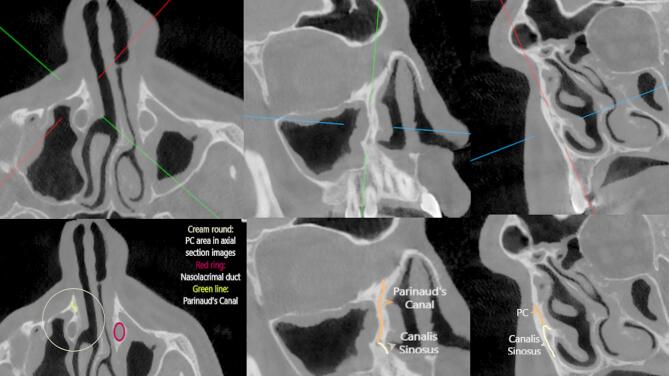

Parinaud管(PC)是位于上颌骨额突骨上的一种结构。在生长期间,鼻中隔的形状和鼻中隔偏曲(NSD)的存在可能影响面部形态学参数。本研究的目的是探讨PC的存在和NSD对面部形态学参数的影响。回顾性分析了200例患者的影像学资料。在CBCT图像上评估PC、NSD和腭眶角。显著性水平设为p = 0.05。在普通人群中PC的发生率较高,且在鼻偏斜角上差异无统计学意义(p < 0.05)。当左PC直径小于1 mm时,NSD角度有统计学意义上的增加(p

Parinaud's canal (PC) is a structure located on the processus frontalis ossis maxilla. During the growth period, the shape of the nasal septum and the presence of nasal septal deviation (NSD) may affect facial morphological parameters. The aim of this study is to investigate the presence of PC and the effect of the NSD on facial morphological parameters. Radiographic images of 200 patients were retrospectively reviewed. On the CBCT images PC, NSD and Palate-Orbita angle were evaluated. The significance level was set at p = 0.05. PC was found to be present at a high rate in the general population and its presence was not significantly different according to the angle of nasal deviation (p > 0.05). The angle of NSD was found to increase statistically when the left PC diameter was 1 mm or less (p < 0.05). The mean Hard Palate - Orbital Angle was 46.66 ± 8.43 degrees in individuals with the right PC while this angle was 36.50 ± 1.65 degrees in those without a canal. his study revealed that PC is common in the general population and has no significant relationship with NSD angle. While a decrease in the diameter of the left Parinaud's canal is observed as the NSD increases, the Hard Palate - Orbital Angle varies depending on the presence of the right PC. These findings indicate PC may play an important role in nasal and orbital anatomy.